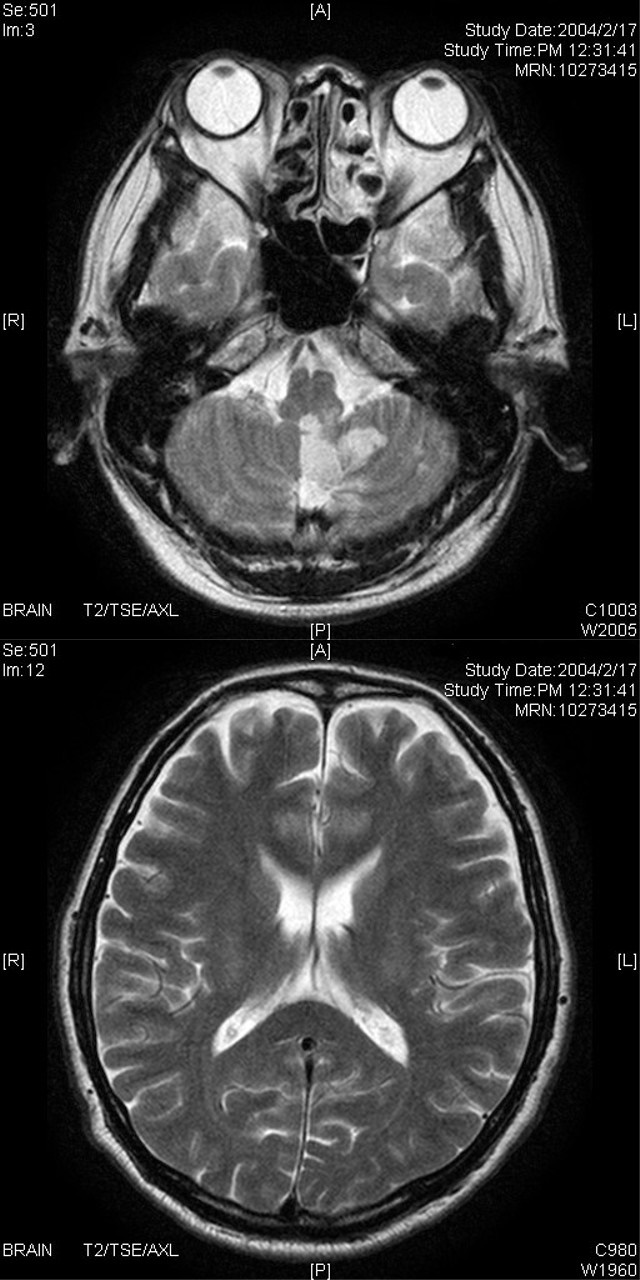

脳ドック

MRI・MRAなどの画像検査により、脳卒中の危険因子や脳腫瘍、認知症などの早期発見を目的とします。自覚症状が出る前に、脳や脳の血管の状態を詳しく検査することは、病気の発症や進行を防ぐことに役立ちます。

Aコース

■頭部MRI・頭部MRA・頚部MRA ■身長・体重・BMI・血圧

■神経内科専門医による診察・結果説明

Bコース

■血液・尿検査 ■心電図・心臓超音波検査